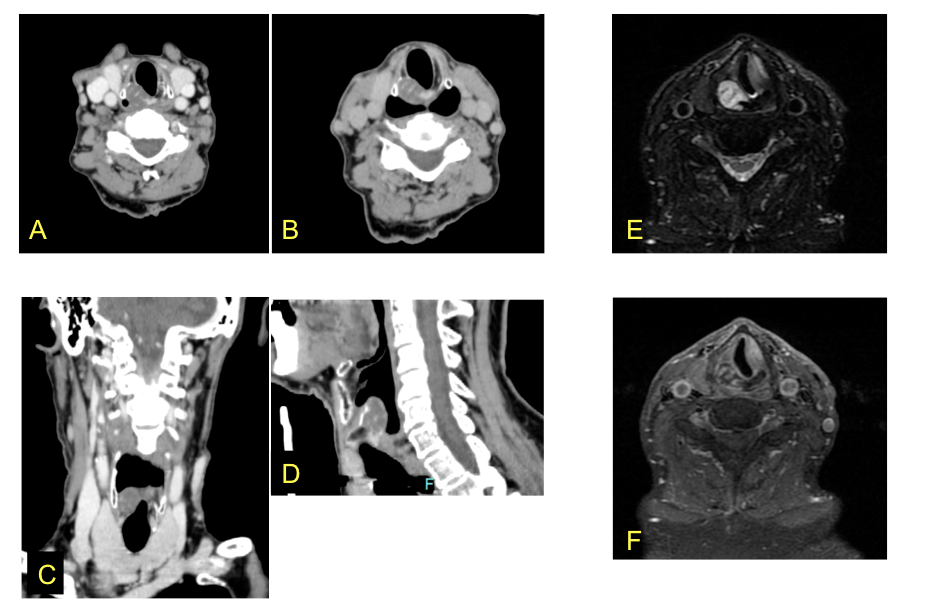

– A, B, C y D. TC de cuello con contraste. Adquisición basal (A y C) y tardía con maniobra dinámica «valsalva modificado» (B y D). Cortes axiales y reconstrucciones coronal y sagital. En plano glótico/subglótico se visualiza una tumoración de baja densidad (flechas) , bien delimitada , que parece depender del ala derecha de la lámina posterior del cartílago cricoides. Muestra crecimiento exofítico, con insuflación y calcificaciones focales en su interior, con escasa captación de contraste. No asocia masa de partes blandas ni signos de infiltración de otras estructuras.

– E y F. RM de cuello. Secuencia T2 con supresión grasa (E) y T1 con supresión grasa con contraste (F), plano axial. La tumoración presenta marcada hiperintensidad en secuencias potenciadas en T2, con tabiques hipointensos. Tras administración de contraste se observa realce periférico y de los tabiques, los cuales parecen estar en relación con las calcificaciones visualizadas en la TC. En la fibrolaringoscopia se visualizaba como una tumoración de asiento submucoso.